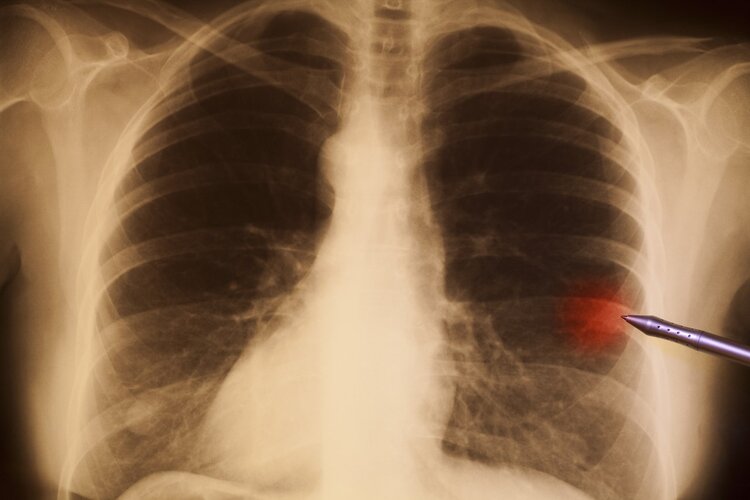

她急忙来到厦门市第五医院求诊,经腹部磁共振一扫检,肚子里竟然藏了个巨大的卵巢肿瘤,直径足足30CM大。

核磁共振扫描结果 图源:厦门广电

幸运的是,经过术中快速病理,发现该肿瘤为良性肿瘤,医生成功地做了手术将肿瘤切除了。